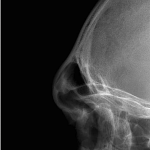

“Aesthetic temporal reduction” (often called temporal narrowing surgery) is a niche craniofacial procedure aimed at reducing the width of the head in the temple region (the area above and slightly behind the eyes). What it targets The temporal region (sides of the skull) Specifically: Temporal bone (outer skull) Temporalis muscle (a chewing muscle that can add bulk) How it’s done Read More…